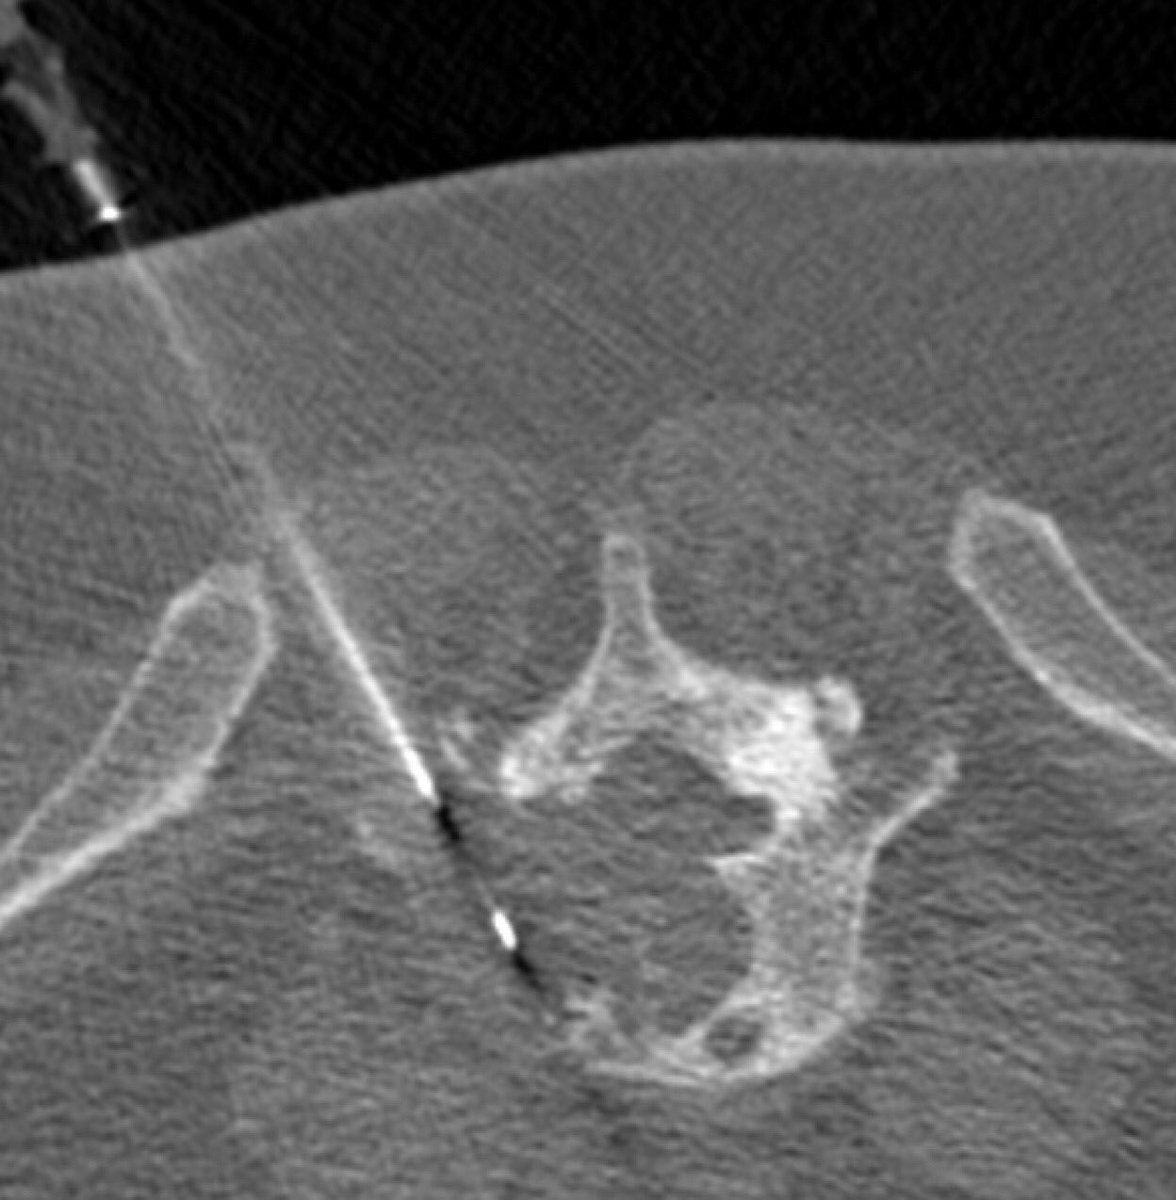

#Irad#SpineRad#NeuroRad: What is wrong with this image? Clue: It happens not so uncommonly. Answer: https://articl.net/resource/percutaneous-spine-biopsy … pic.twitter.com/0lwm1meNhT